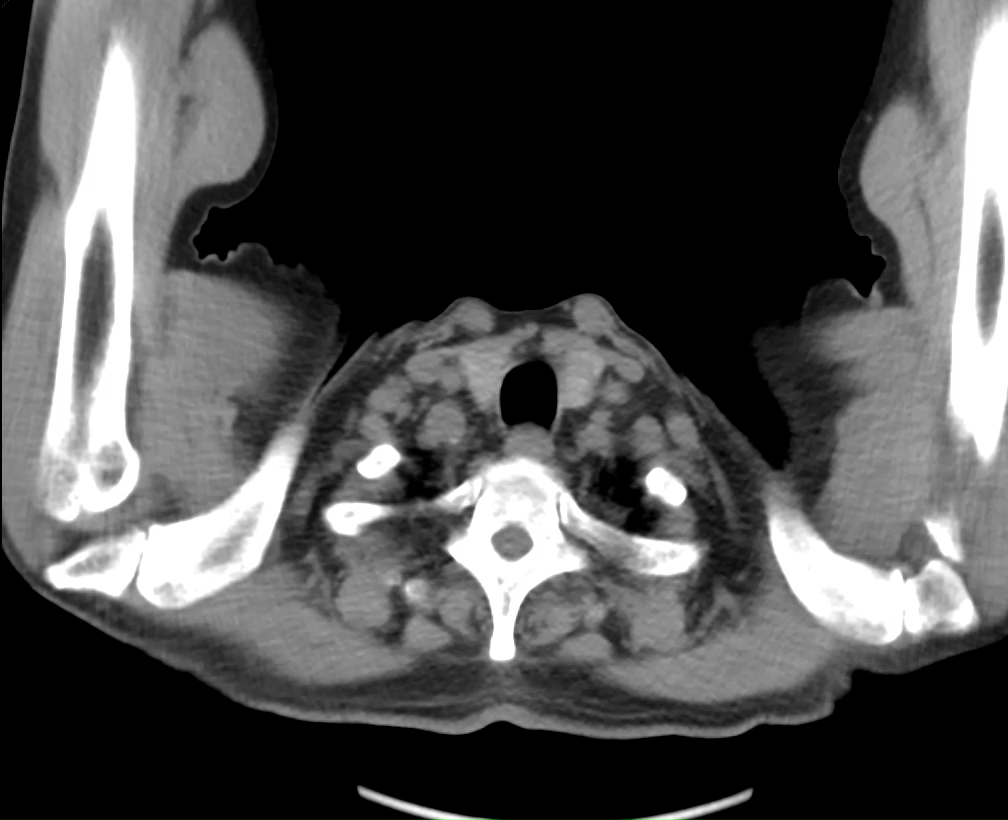

2025-09-14CT胸部平扫:1、右肺上叶肺门结构不清伴纵隔淋巴结增多,请结合临床病史及纤支镜检查、随诊;2. 右肺上叶条索、结节灶(伴部分钙化),考虑纤维增殖性病变?,随诊;3. 两肺小结节及钙化灶,两肺散在少许炎性改变, 请结合临床、随诊。

电子支气管镜:局麻满意后经鼻进镜,气管:气管通畅,隆突锐利,粘膜光滑。

右侧:右主支气管、右中间段、右中叶、右下叶及各级支气管管腔通畅,粘膜光滑,未见新生物;右肺上叶开口狭窄,表面粘膜充血水肿,疑似外压,未见明显新生物,在此处予以刷检、灌洗,送细菌学、细胞学及tNGS检查。

左侧:左主支气管、左下叶支气管及各级支气管管腔通畅,粘膜光滑,未见新生物;左上叶开口粘膜表面稍充血伴水肿,开口狭窄。术毕,术中无活动性出血,患者安返病房